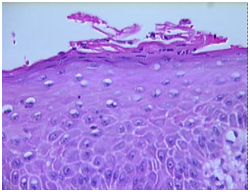

Figure 5 Fungal spores and pseuodohyphae invading the squamous epithelium- oral cavity.

Figure 6 Candidial hyphae with spores dispersed with the stratum corneum.

Histopathology: elucidates an epithelial entrenchment by the Candida hyphae and fungal spores accompanied with chronic inflammation, hyperkeratosis, parakeratosis and orthokeratosis.1,6 Hyperplasia with Candida inflammation generally elucidates a dysplastic metamorphosis.1,6

Chronic candidiasis: Prominent hyperkeratosis, pseudo-epitheliomatous hyperplasia, compressed orthokeratosis and a scaly encrustation may appear.5,6 Fungal spores and hyphae may be delineated in the absence of a Periodic acid Schiff (PAS) stain. Granulomatous dermatitis may also emerge with indeterminate granulomas comprising of lymphocytes, plasma cells, epitheloid cells and sporadic giant cells.5,6